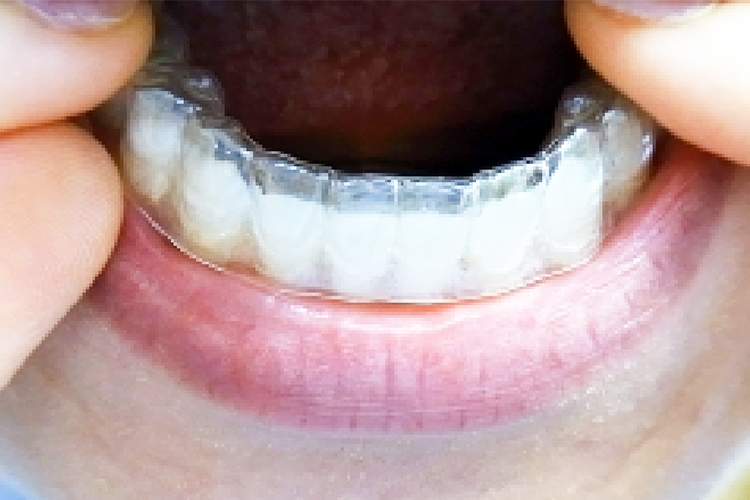

コア歯科クリニックでは、マウスピースによる治療を行っております。

マウスピースを使用することで、舌が喉の奥へ落ちづらくなり、気道が確保され、いびきや無呼吸を防ぐことに繋がります。また鼻呼吸への習慣付けの効果もあります。

潜在的な無呼吸症の患者様には、精密検査を受けていただくため耳鼻科をご紹介し、耳鼻科での検査を経てから保険適用のマウスピースを用いた治療を行っています。精密検査は1日程度の入院が必要となります。

また、いびきの症状のみを改善したい患者様は、自費治療でのマウスピース治療を行うこともできます。